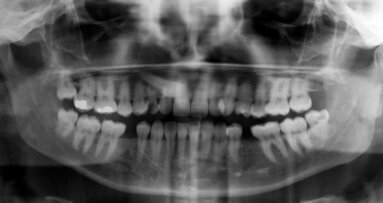

In your webinar, you will also speak about implant stability quotient (ISQ) measurement and resonance frequency analysis by Osstell. How can these tools support dental professionals in the decision-making process? Surprisingly, we still consider ISQ measurement as a new tool! It is such an old concept and has been well studied and validated for many years and documented in numerous articles. It is an indispensable method of objectively evaluating the primary stability of the implant, the most important parameter of success. It helps the dentist to make the right decisions about surgical procedures and the timing of postoperative procedures. In addition, it is very useful in explaining to the patient what we do and why. Despite the fact that we do have this great tool, and the fact that many clinicians propose immediate post-extraction implants or immediate loading, these systems are still available in too few practices.

Immediate loading is increasingly being offered as a routine method in dental implant surgery. However, according to Dr Mauro Labanca, it should be handled with more caution, as research has demonstrated that its success rates do not always match those of traditional methods. In an upcoming free webinar on 10 March, he will explain how to ensure qualitative care while applying scientifically proven tools which enable clinicians to obtain objective data on implant stability that is comparable over time.